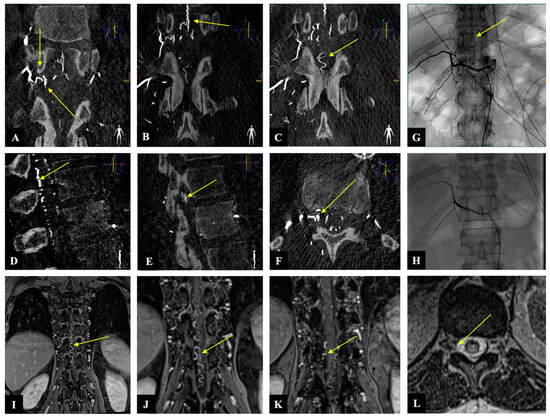

Figure 3. Case illustration: The images of three-dimensionally reconstructed digital subtraction angiography (DSA) of the spine ((AC): coronary, (D,E): sagittal, and (F): axial) show the fistula location at the level of Th 12 on the right side as well as the flow voids (yellow arrows). Image (G) shows the preoperative SDAVF in conventional DSA with flow voids (yellow arrow), and image (H) demonstrates the postoperative absence of the SDAVF. The magnetic resonance angiography images ((IK): coronary and (L): axial) show the fistulous point at the level of Th 12 on the right side as well as the flow voids (yellow arrow).

2.3. Illustrative Case

A 54-year-old woman presented with a one-month history of progressive gait disturbance, bowel and bladder dysfunction, and saddle anesthesia. The possible walking distance without a break was 200 m. There was also a slight paresis of the hip flexor and big toe extensor on the right side (ASIA-MS: 98, mALS: 6). The patient was admitted to the hospital by her general practitioner. On the day of admission, we performed a spinal MRI/MRA and DSA, which showed a DSAVF at the Th12/L1 level on the right. On the same day, the patient developed a rapidly progressing high-grade paraparesis with complete urinary and fecal incontinence (ASIA-MS: 70, mALS: 11). Emergency surgical treatment was performed via hemilaminectomy and closure of the right Th12 SDAVF without complications. Post-treatment DSA showed complete obliteration of the fistula, and MRI revealed no further flow voids and a reduction in myelopathy. The patient could be mobilized on the ward floor. After 2 months, the patient presented to the emergency room without motor deficits (ASIA-MS 100) but with a renewed deterioration of gait (gait score in mALS: 2) and persistent saddle anesthesia and leg paresthesia. The MRI showed further regression of the myelopathy and no signs of SDAVF recurrence. The gait disturbance improved spontaneously, and the patient was discharged home. At the second follow-up assessment (after 6 months), the MRI showed no myelopathy, but the patient still had a gait disturbance. A return to work was no longer possible. This case is the only one from our center with a rapid deterioration within one day, which we do not know in this form for this disease (Figure 2 and Figure 3).